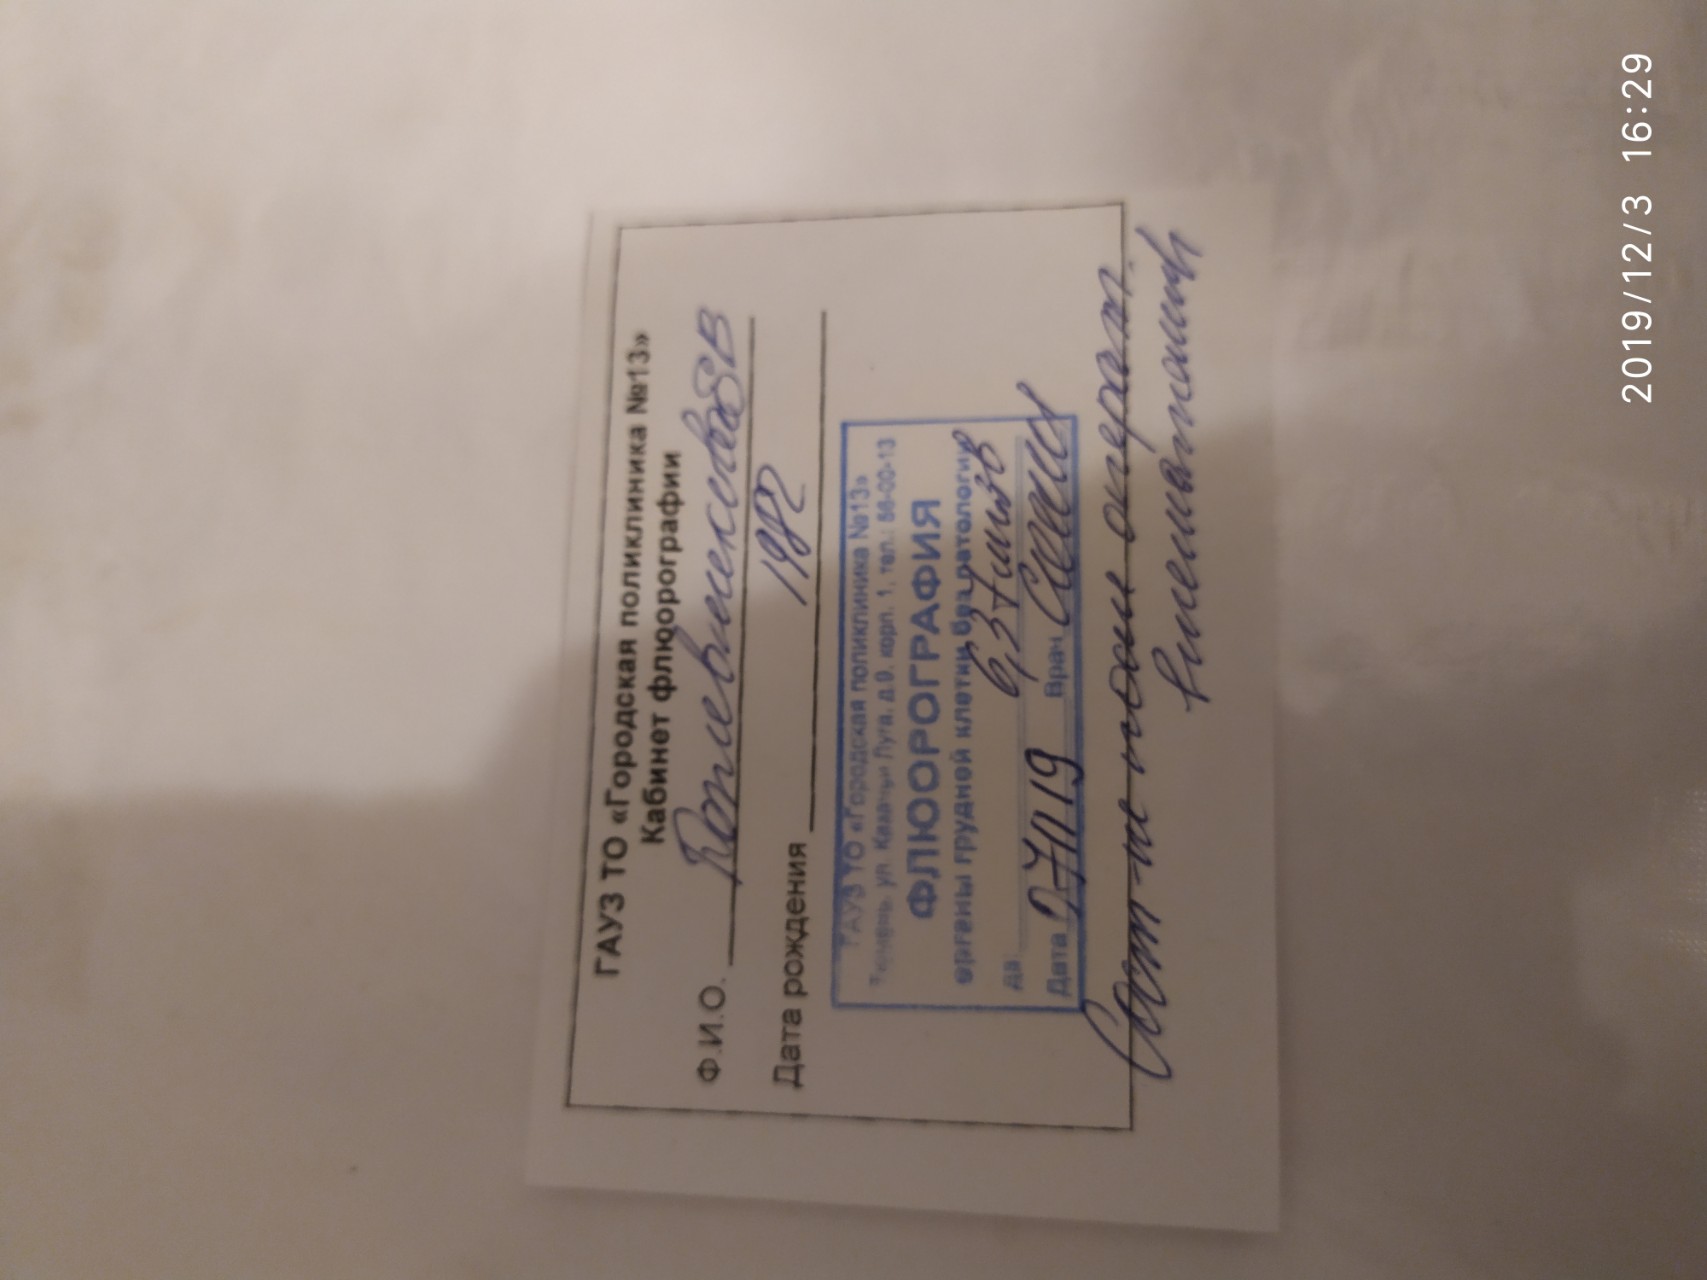

Фотографии рентгеновских снимков без необходимости направления от врача